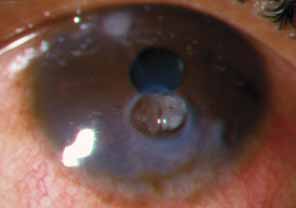

The current number of procedures performed on an annual basis is decreasing slightly; a total of 32,744 corneal transplants were performed in 2002, marking the first time since 1986 that the number of procedures performed has been less than 33,000.1 This downward trend has coincided with the decrease in incidence of pseudophakic corneal edema (PCE) (Fig. 1) and aphakic corneal edema (ACE). The percentage of PKs performed to treat PCE has dropped from 19.8% in 2001 to 18.4% in 2002, which was the lowest percent reported in this category in 15 total years of tracking by the Eye Bank Association of America (EBAA). It is possible that this decrease reflects improved cataract removal technique and technology, such as phacoemulsification and posterior chamber intraocular lens placement. The indications for PK have shifted over the past several decades, with PCE the most common indication since 1980, whereas keratoconus (Fig. 2) and ACE were the most common indications prior to 1980.2 Data is tracked for a total of 16 indications for transplant by the EBAA. Pseudophakic corneal edema, keratoconus (particularly in younger patients), Fuchs' endothelial dystrophy (particularly in older patients), and regrafting secondary to rejection or other reasons currently sit atop the list of indications for PK.

Fig. 1 Pseudophakic corneal edema is the leading indication for penetrating keratoplasty in the United States.

Fig. 2 Keratoconus is one of the most common indications for penetrating keratoplasty. Descemet's tears may occur spontaneously in this condition, leading to acute hydrops.